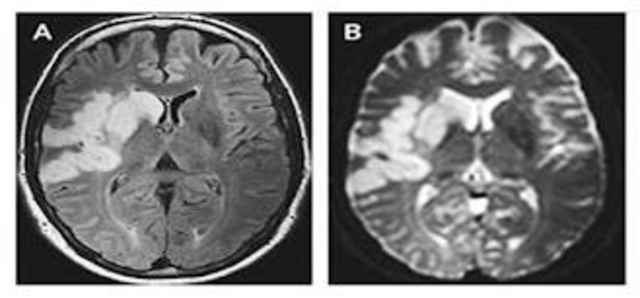

• First Therapy for Ischemic Stroke

First Therapy for Ischemic Stroke

Until this study was published, stroke was addressed primarily by prevention rather than treatment. In this trial, 624 patients presenting to the hospital within 3 hours after the onset of stroke symptoms were randomized to receive either doses of less than 0.9 mg of recombinant human tissue plasminogen activator (t-PA) per kilogram of body weight or placebo. Patients treated with t-PA were at least 30% more likely to have minimal or no disability at 3 months.